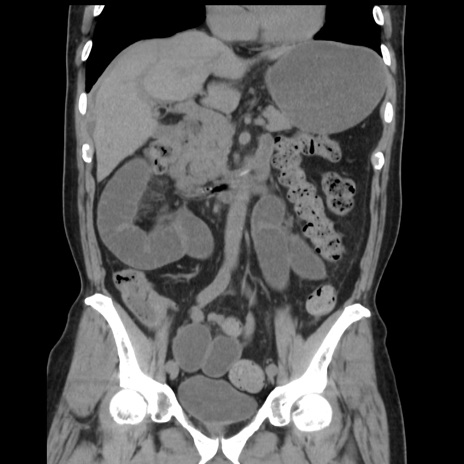

症例16(冠状断像)

【症例】 70歳代男性

【主訴】 腹痛、嘔吐

【現病歴】 約1ヶ月前より間欠的に腹痛と嘔吐あり、当院消化器内科を受診したところCTで多発する肝臓のLDAを指摘され、精査中であった。以降は消化器症状は安定していたが、2日前より嘔気と腹痛があり、同日より排便・排ガスが消失した。改善認めず、 本日、救急外来を受診した。

【既往歴】 大腸ポリープ切除後。

【身体所見】意識清明・会話良好、BT 36.3℃、BP 127/80mmHg、 P 80bpm、腹部:膨満あり、平坦・軟、上腹部正中および下腹部正中に圧痛あり、反跳痛なし、筋性防御なし。

【データ】WBC 7200、CRP 0.77